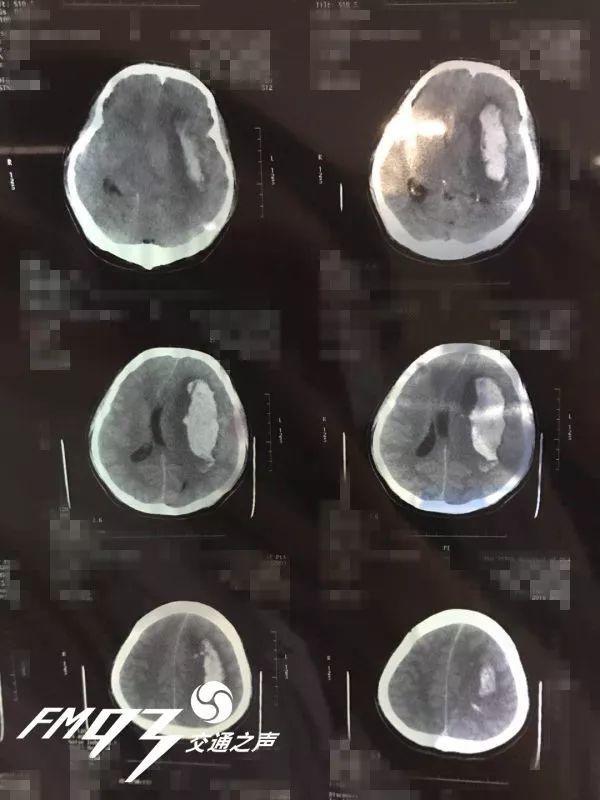

Khi đến viện, các bác sĩ đã tiến hành chụp CT não, kết quả cho thấy có xuất huyết nội sọ, lượng máu chảy đến 90ml. Thông thường nếu lượng máu chảy đạt hơn 30ml đã phải phẫu thuật, trường hợp của bệnh nhân còn nhiều hơn gấp 3 lần, có nguy cơ bị bại não do áp lực nội sọ quá cao, cần tiến hành phẫu thuật càng sớm càng tốt.